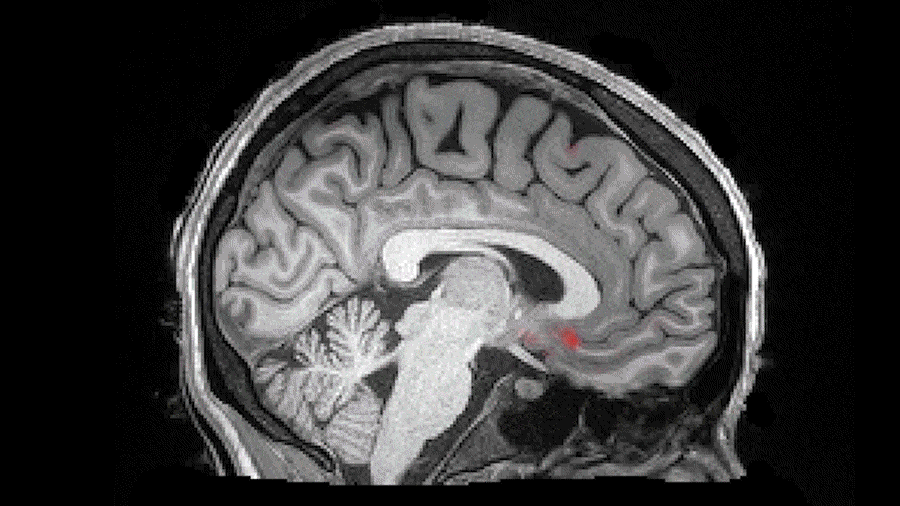

Daarnaast krimpen je hersenen gepulseerd een beetje in volume doordat er wat minder bloed in wordt gepompt, zodat de ruimtes tussen je hersenen groter worden en er makkelijker vloeistof tussendoor kan. Dit uitrolbare 'riool' noemen we het glymfatisch systeem.

Tijdens diepe slaap, vallen golven van hersenvocht (blauw) samen met tijdelijke afname van de bloedstroom (rood). Minder bloed in de hersenen betekent meer ruimte voor de vloeistof om gifstoffen weg te voeren .Credits: Fultz et al. 2019

De opgestapelde gifstoffen en adenosine worden weggewassen. Letterlijk brainwashing dus.